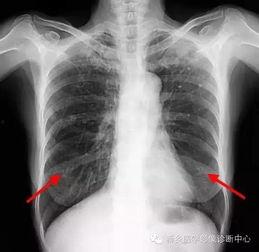

胸片检查是诊断肺部疾病的重要手段。通过观察肺部影像,医生可以初步判断患者是否患有肺炎、肺结核、肺癌等疾病。

3. 胸部外伤诊断